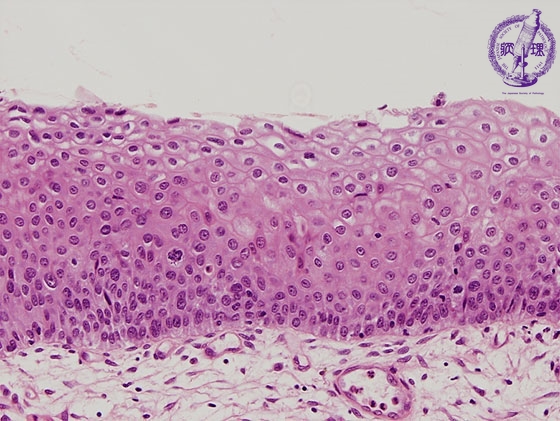

- ★(4)Cervical intraepithelial neoplasia

Histology (HE stain, high power): Moderate dysplasia (CIN2). Atypical cells with nuclear enlargement and high nuclear density proliferated from the side of basement membrane to basal side through a 2/3 thickness of the epithelium.